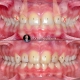

درمان ارتودنسی بدون جراحی و بدون کشیدن دندان در کیس دیپ بایت همراه با کنت اکلوزال و باکال کریدور های وسیع در مدت ۲۰ ماه انجام شد.

Non surgical and non extraction orthodontic treatment of deepbite case with occlusal cant and large buccal corridors done within 20 months.